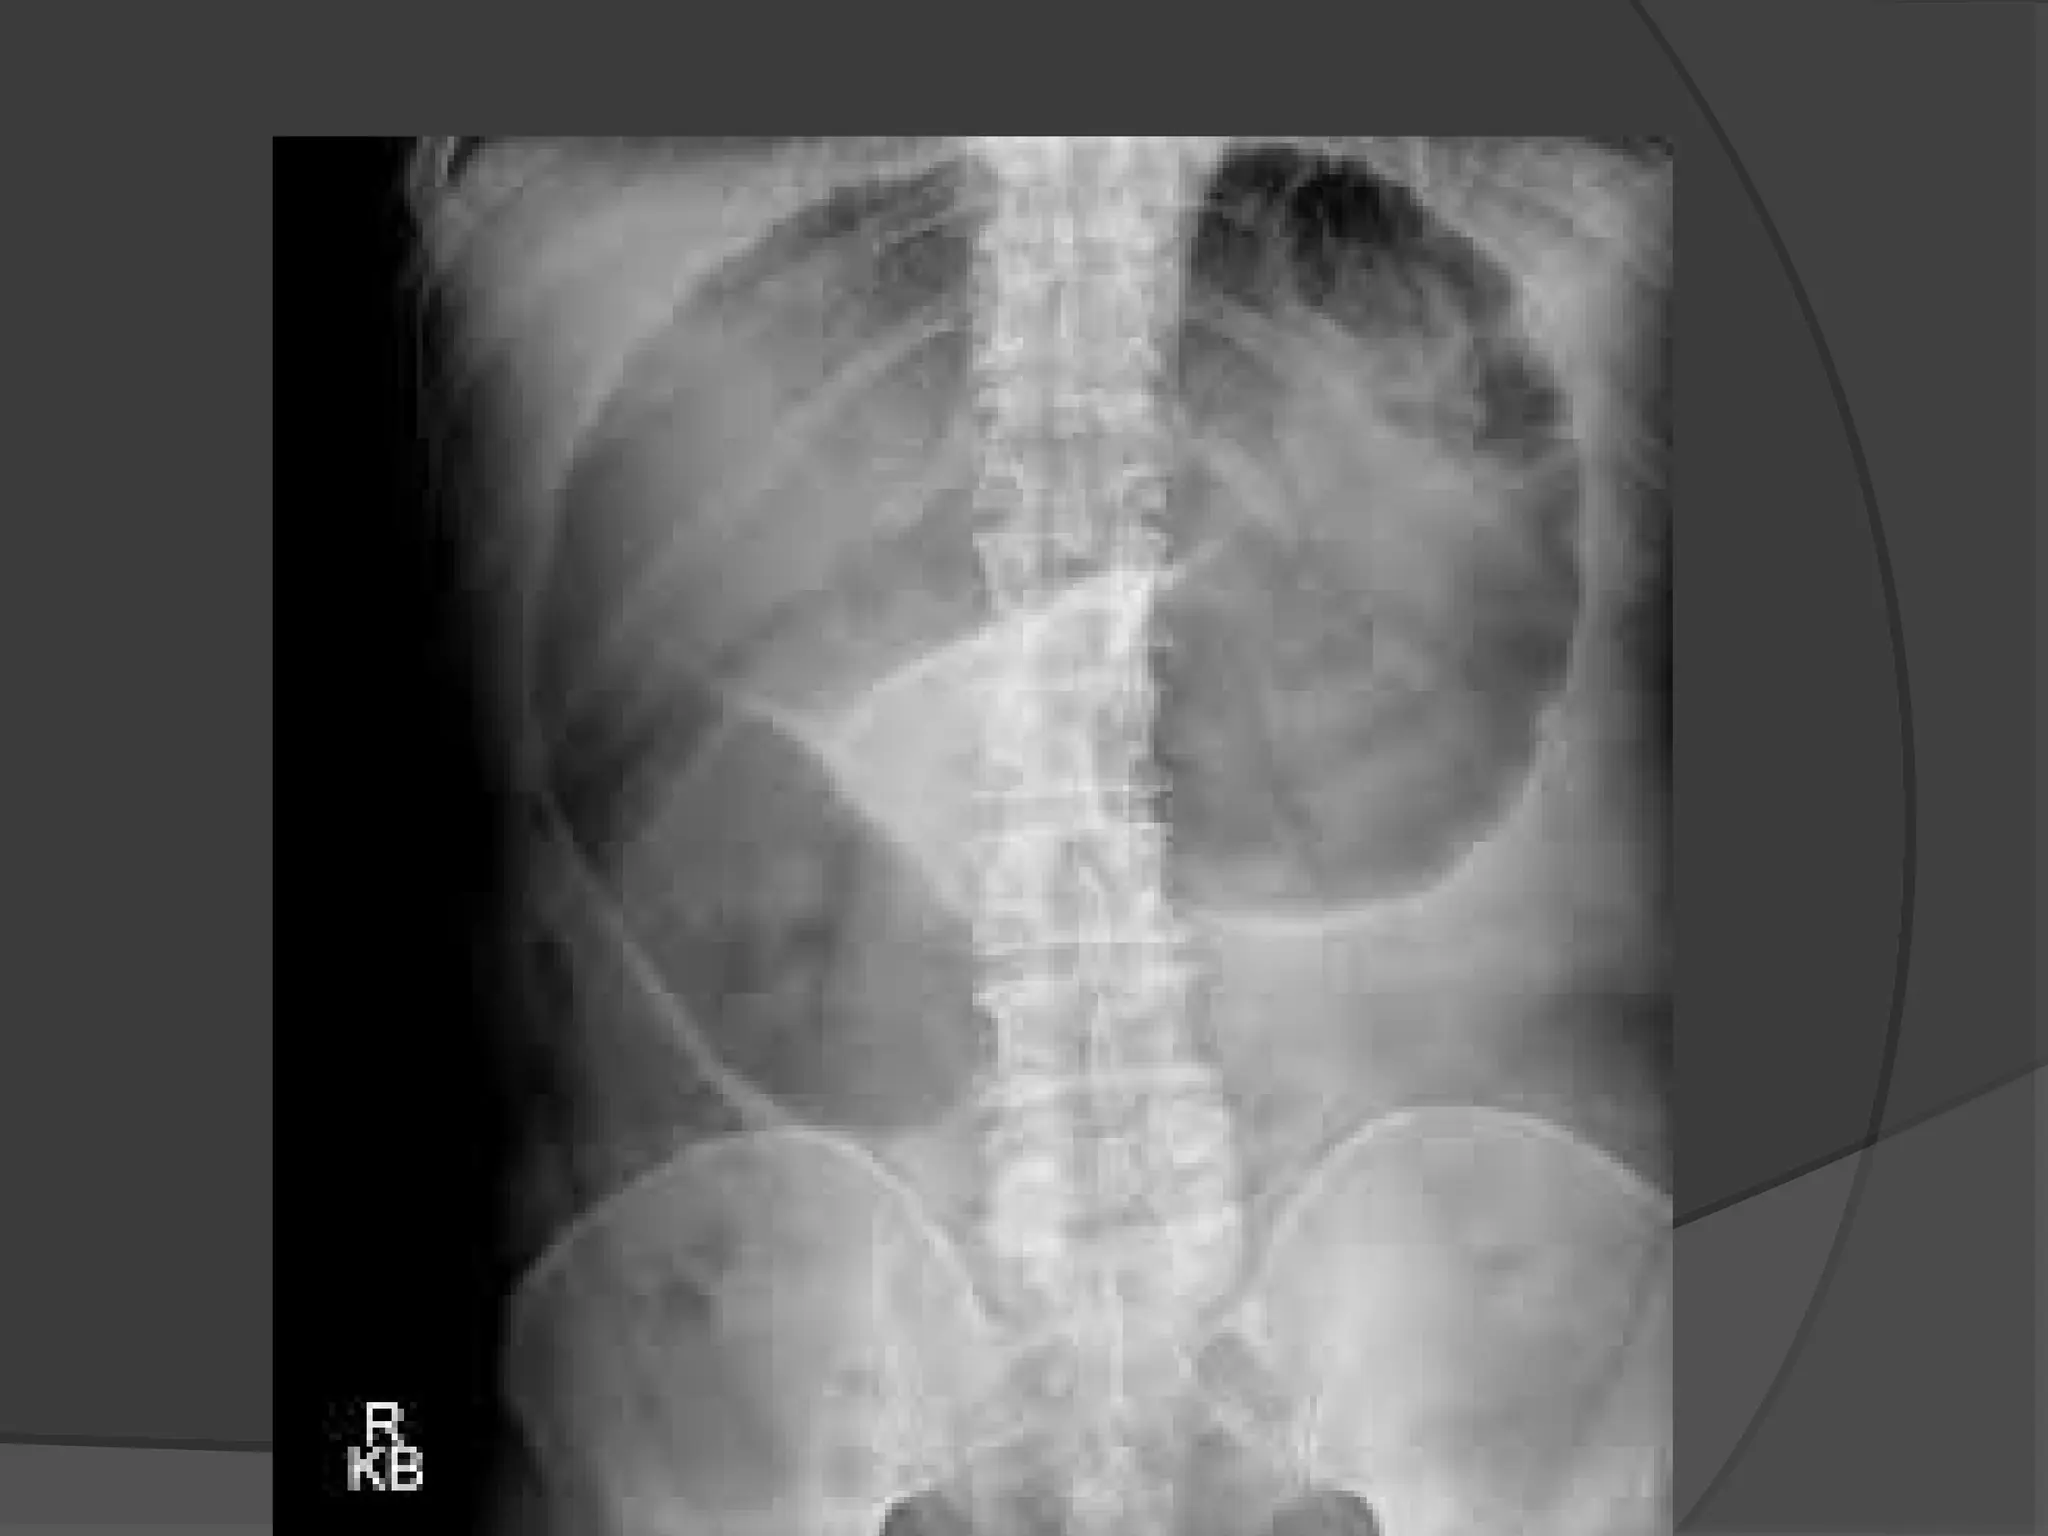

Radiological diagnosis is based on a supine

abdominal film

 Obstructed small bowel -straight segments

that are generally central and lie

transversely. No gas is seen in the colon.

 Jejunum -valvulae conniventes

 Ileum -featureless

 Caecum-a rounded gas shadow in the right iliac

fossa.

 Large bowel- haustral folds

X-RAY

 Small Bowel

Obstruction is

suggested by a

“ladder” pattern, when

obstruction occurs,

both fluid and gas

collect in the intestine.

 They produce a

characteristic pattern

called air-fluid levels.

The air rises above

the fluid and there is a

flat surface at the air-

fluid interface.

 Distended Large

Bowel Tends to lie

peripherally and to

show the

Hustrations of the

Taenia Coli.